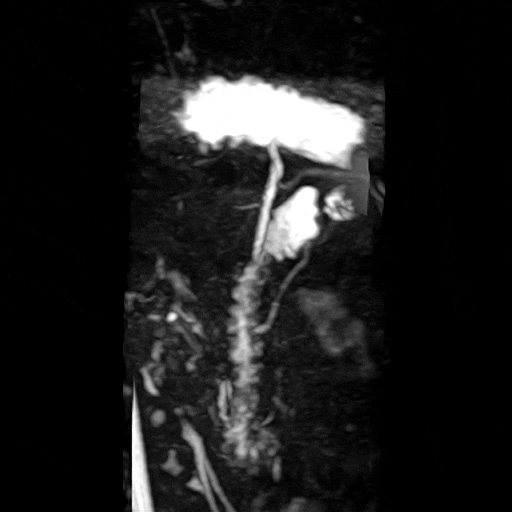

• 췌장MRI: 8mm 미세병변 췌장MRI: 8mm 미세병변

• 췌장MRI: 관상면 영상 췌장MRI: 관상면 영상

췌장몸통 쪽으로 약 0.8cm 가량의 물혹이 보이며, 이는 췌장담도와 연결성이 보이고 있습니다. 이는 췌관내유두점액낭종으로 생각이 되며, 이에 대해서 6개월 간격으로 추적 관찰을 하기로 했으며, 경과를 보고 치료시기를 결정하기로 했습니다.